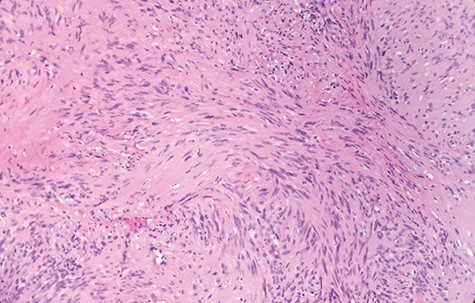

Macroscopically, the tumor appeared encapsulated, rubbery and pink-tan in color. Microscopic examination reveals that tumor composed of biphasic spindle hypercellular Antoni A areas and hypocellular Antoni B areas (Fig. 1). Higher magnification reveals that spindle tumor cells are narrow, elongate, wavy with tapered ends interspersed with collagen fibers (Fig. 2). Immunohistochemical staining revealed that most tumor cells reacted strongly for S-100 protein (Fig. 3). Combined with immunohistochemical profile, these histological features are diagnostic of benign schwannoma. Patient was discharged home on the same day as the operation. At the 1-month follow-up, he was symptom free, without any pain or sensory disturbances.

Higher magnification reveals spindle tumor cells are narrow, elongate, wavy with tapered ends interspersed with collagen fibers (×20).